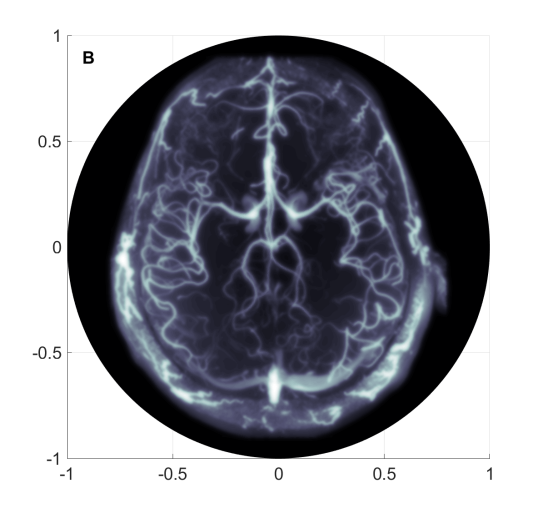

Figure 3 displays a coarse mesh used for the FEM, the exact pressure profile to be reconstructed and the boundary measurements. These measurements were synthetically generated by applying the discrete version of the forward operator using the aforementioned numerical method for the wave equation. The FEM for the reconstruction procedure has 109,762 degrees of freedom and 6,400 time steps covered the time window for . The mesh employed to generate the measurements was more refined, with mesh size approximately half of the mesh size employed in the reconstruction steps, and the data was down-sampled to the reconstruction mesh using linear interpolation.

In order to visualize the impact of improperly modeling the piezoelectric measurements, we have implemented two reconstructions of the initial acoustic profile. In both case, the same synthetic measurements are used. For the first reconstruction, we properly interpret the given measurements as generated by the piezoelectric model (28) and carry out the reconstruction using Algorithm 1. After 50 iterations we obtain a relative error of . For the second reconstruction, we improperly interpret the measurements as the Dirichlet data of the pressure field. This is the naive model commonly employed by others but inconsistent with the piezoelectric transduction. The reconstruction is carried out using Algorithm 1 modified by setting which is equivalent to assuming that the measurements are Dirichlet data. After 50 iterations we obtain a relative error of . The error profiles for both reconstructions are displayed in Figure 5.